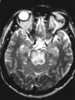

CSF-intensity brainstem lesion

A brain tumor occurs when abnormal cells form within the brain. There are two main types of tumors: cancerous (malignant) tumors and benign (non-cancerous) tumors. [Source: Wikipedia ]